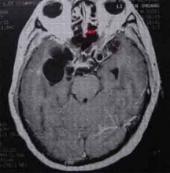

腦寄生蟲病

628健康網為您分享有關腦寄生蟲病的癥狀,腦寄生蟲病的治療方法,腦寄生蟲病的預防知識,腦寄生蟲病的癥狀圖片,腦寄生蟲病...